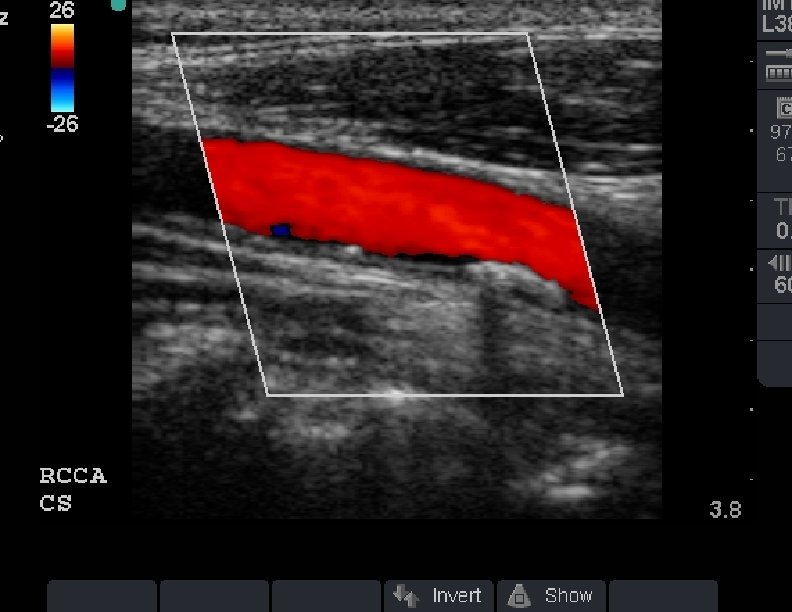

Plaque with color doppler